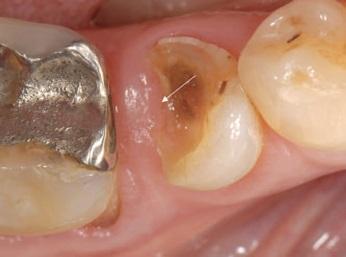

Restorative Treatments for Lesions with Subgingival Margins

Various approaches have been proposed for clinical cases where the margins of the cavity are subgingival.

- When asked about an emerging technique to restore the tooth called coronal marginal relocation (CMR), deep margin elevation (DME) or Proximal Box Elevation (PBE), about half of the practitioners have heard of (25%) or used the restorative technique (28%), but most were not aware of it (48%).